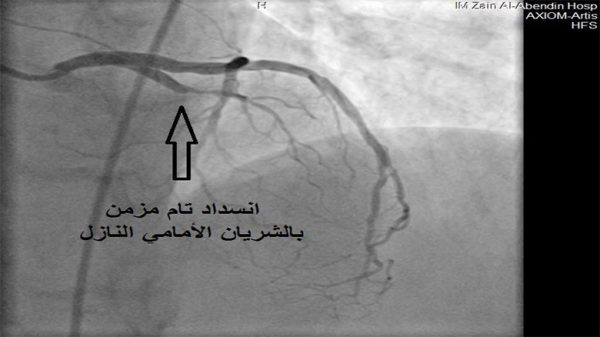

الحكمة – متابعة: أعلن مستشفى الإمام زين العابدين عليه السلام التابع للعتبة الحسينية المقدسة نجاح فريق القسطرة القلبية في فتح انسداد مزمن في الشريان الأمامي النازل لمريضة تبلغ من العمر 70 عاما.

وقال أخصائي القسطرة القلبية الدكتور فرهود الصوص ان “المريضة راجعت العيادة القلبية وهي تشكو من الم صدري خانق منذ عدة أشهر, وبعد إجراء قسطرة قلبية لها تبين وجود انسداد تام مزمن في الشريان الأمامي النازل”.

وأضاف “تم فتح الانسداد في الشريان باستخدام البالون, وزرع شبكة دوائية في مكان الانسداد, والحصول على نتيجة نهائية بعودة جريان الدم داخل الشريان بشكل طبيعي”.